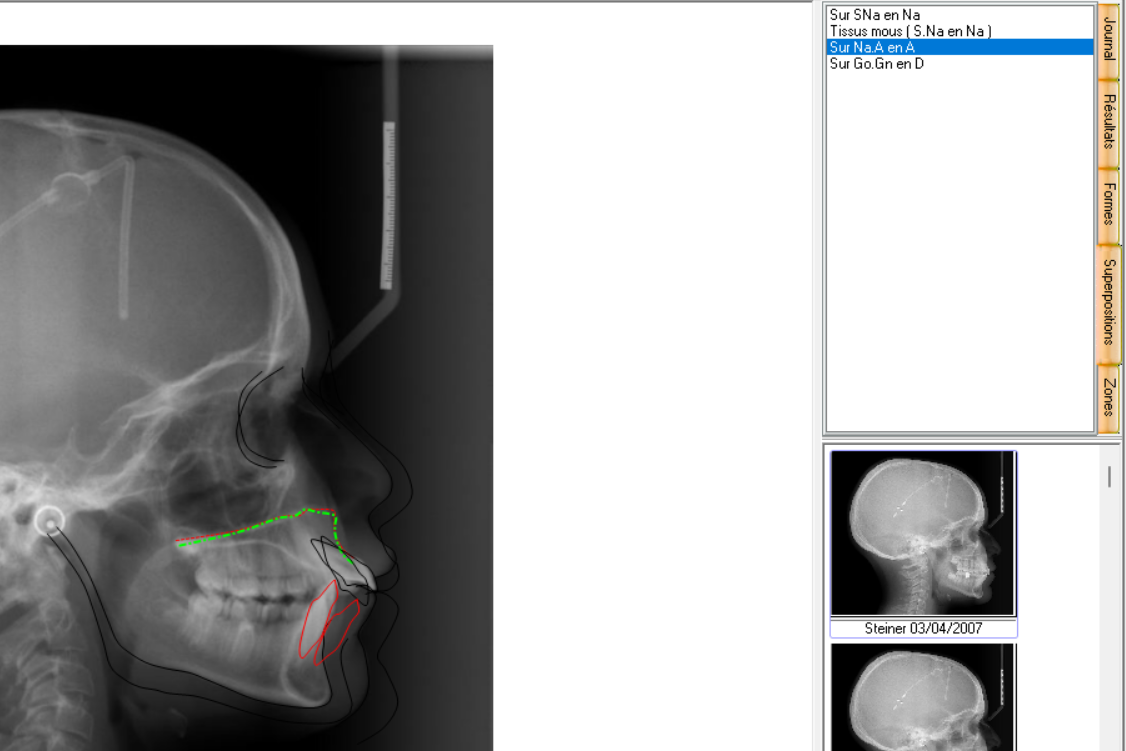

Pour choisir une superposition avec un plan (donc points) différent, allez sur onglet Superposition a droite de la fenêtre générale.

De cet onglet vous aurez accès à la liste des plans de superposition.

Sur cet exemple, nous choisissons Sur Na.A en A.